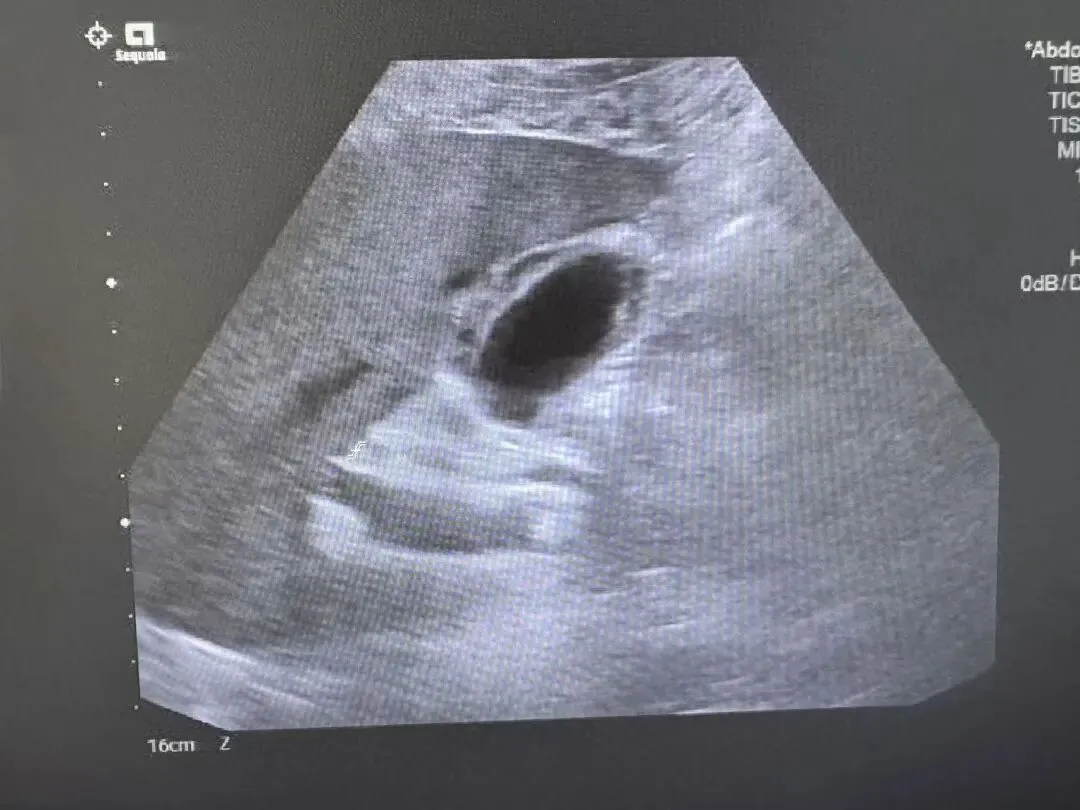

胆囊息肉样病变

又称为胆囊隆起样病变,包括胆囊胆固醇沉着症、胆囊腺肌增生症、胆囊腺瘤、胆囊炎性息肉。

胆囊壁上等回声乳头样结构突向胆囊腔

胆囊炎性息肉

胆囊壁增厚、毛糙, 胆囊壁上多个等回声乳头样结构突向胆囊腔